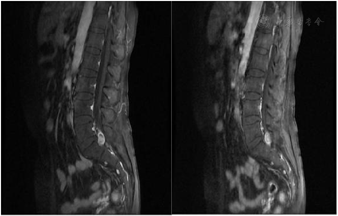

例2于2017年4月3日骨科门诊行磁共振腰椎MR1.5T增强扫描(图1)示L5~S1水平椎体内左侧神经根走行处病灶,考虑神经鞘瘤可能大。L5~S1椎间盘突出。腰椎退变。2017年4月10日多排CT腰椎平扫(椎间盘L2~S1)示:L5~S1水平椎体内左侧神经根走行处见类圆形稍低密度影,大小约1.8 cm×1.1 cm。L5~S1水平椎体内左侧神经根走行处病灶,结合2017年4月3日腰椎MR,考虑神经鞘瘤可能。2017年4月15日术后病理:(L5~S1神经根)卵圆形肿物1枚,大小1.5 cm×1.0 cm×1.0 cm,肿物切面灰白质地韧。镜下病理诊断:考虑神经源性肿瘤,大小1.5 cm×1.0 cm×1.0 cm。

MMNST的临床表现取决于肿瘤发生的部位和生长速度,其可分为砂砾体型和经典型,砂砾体型和经典型的临床病理特征相似,砂砾体型MMNST发病率为10%~40%,患者可伴有颜面部皮肤色素沉着,心脏黏液瘤和内分泌功能亢进。有研究表明,约50%的Carney综合征(Carney complex,CNC)与砂砾体型MMNST相关[4]。CNC是一种常染色体显性遗传病,于1985年首次报道,目前的研究认为,CNC与17号染色体的长臂基因PRKAR1A基因有关[5]。因此MMNST的发病与PRKAR1A基因也存在一定相关性。本文2例患者分子病理结果提示,未发现PRKAR1A基因突变,且仔细观察,本文2例患者镜下均未见砂砾体(分层状的钙化小球),故暂不考虑CNC的诊断。MMNST肿瘤内含大量黑色素颗粒,黑色素颗粒中的稳定自由基团在磁场中呈顺磁性,减少核磁中T1、T2的弛豫时间,因此表现出T1W1高信号、T2W1极低信号[6,7]。因此核磁是诊断MMNST的首选影像学检查方法。